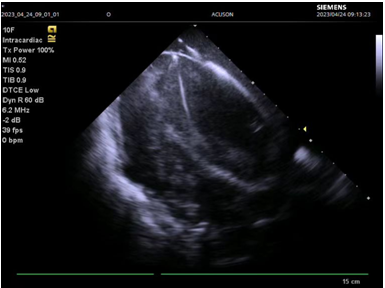

此例手术由姚晓伟主任医师、韩稳琦主治医师、赵永勇主治医师通过心腔内超声指导下进行,通过心腔内超声精准构建心脏模型、直视下穿刺房间隔,后通过心腔内超声及左心房造影寻找狭窄的二尖瓣瓣口,并指引二尖瓣球囊扩张导管顺利经狭窄的二尖瓣口至左心室,在心腔内超声的指引下选择最佳位置以26mm球囊导管反复扩张狭窄的二尖瓣。术后第二天复查心脏超声,患者二尖瓣瓣口面积由术前0.67cm2扩大到术后1.69cm2,二尖瓣跨瓣压差由术前22mmHg降低至术后的16mmHg,左房前后径由术前94mm减小至术后92mm,左房左右径由术前109mm减小至术后102mm,并且球囊扩张后未引起明显的二尖瓣反流,患者心功能明显改善,自觉症状明显好转出院。

图三:心腔内超声指导下成功穿刺房间隔